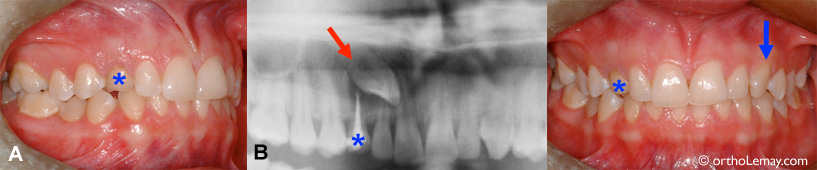

Cas 1 : Cette jeune fille de 15 ans aurait une occlusion très acceptable si ce n’était de la présence d’une canine supérieure droite qui est incluse au palais.

(A) L’occlusion générale est excellente, mais on remarque la présence d’une canine temporaire supérieure droite (*).

(B) La radiographie révèle la présence de la canine incluse qui est en fort mauvaise position (flèche rouge). Ce problème aurait pu être évité ou minimisé. La flèche bleue indique la canine du côté opposé qui est sortie normalement. (Fille – 15 ans)

• Ce problème était certainement visible sur une radiographie panoramique dès l’âge de 8-9 ans et aurait pu être évité ou du moins minimisé avec une supervision adéquate pendant l’éruption des dents et le développement dentaire.

• La canine temporaire aurait dû être extraite il y a plusieurs années pour créer de l’espace et guider la canine permanente vers l’arcade dentaire. Le fait d’avoir gardé la dent temporaire aussi longtemps a contribué à diriger la canine permanente vers le palais.

• À noter que la canine temporaire a déjà été problématique puisqu’un traitement de canal a été effectué sur cette dent (zone blanche visible dans la racine de la dent sur la radiographie). Le dentiste a fait cette procédure pour préserver la dent temporaire quand il aurait été préférable de simplement l’extraire et ainsi tenter d’influencer la direction de la canine permanente. En comparaison, la canine du côté opposé (flèche bleue) est sortie normalement.

• Bien qu’une seule dent soit principalement affectée, l’intervention pour dégager et loger la canine incluse dans l’arcade dentaire est complexe, longue et coûteuse pour cette patiente. Une bonne supervision aurait été plus simple et aurait probablement diminué la nécessité d’avoir recours à des corrections orthodontiques pendant l’adolescence.